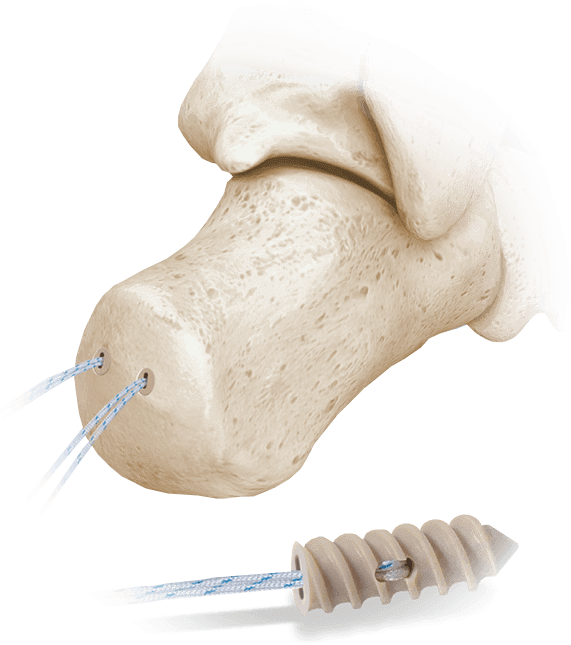

Hercules® Sistema de anclaje de sutura completamente roscado

Anclaje de PEEK con sutura Bightforce™ para una variedad de aplicaciones de fijación de tejidos blandos.

Aplicaciones:

- reparación del tendón de Aquiles

- Reconstrucción del ligamento metatarsiano y del mediopié

- Reinserción de tejidos blandos en el retropié y el antepié

Ventajas Clave:

- Disponible en tamaños de 2,0 mm, 2,5 mm, 3,5 mm, 4,5 mm y 5,5 mm

- PEEK radiotransparente para mayor claridad de imagen

- Se entrega estéril, precargado con sutura BightForce™ y ensamblado a un controlador

- Diseñado para una excelente resistencia a la extracción y una fijación segura